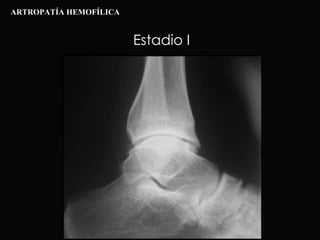

Estadio I ARTROPATÍA HEMOFÍLICA

Estadio II ARTROPATÍA HEMOFÍLICA